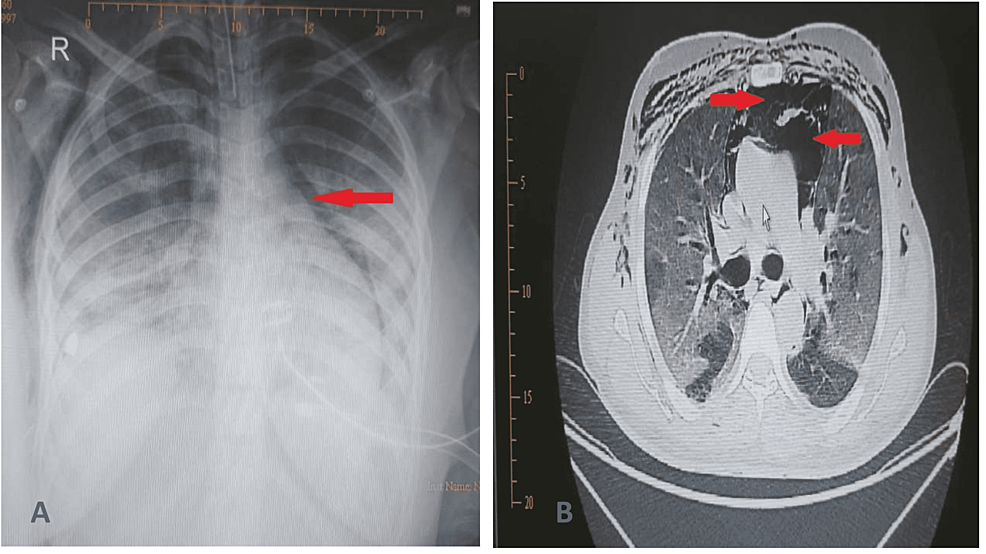

From www.cureus.com

Pulmonary Barotrauma in COVID19 Patients Experience From a Secondary Care Hospital in Oman What Is Barotrauma Lungs pulmonary barotrauma is the presence of extra alveolar air in. pulmonary barotrauma from invasive mechanical ventilation refers to alveolar rupture due to elevated. barotrauma happens when sudden changes in barometric (air) or water pressure damage your body. barotrauma is physical tissue damage caused by an unrelieved pressure differential between a surrounding gas or fluid and an. What Is Barotrauma Lungs.